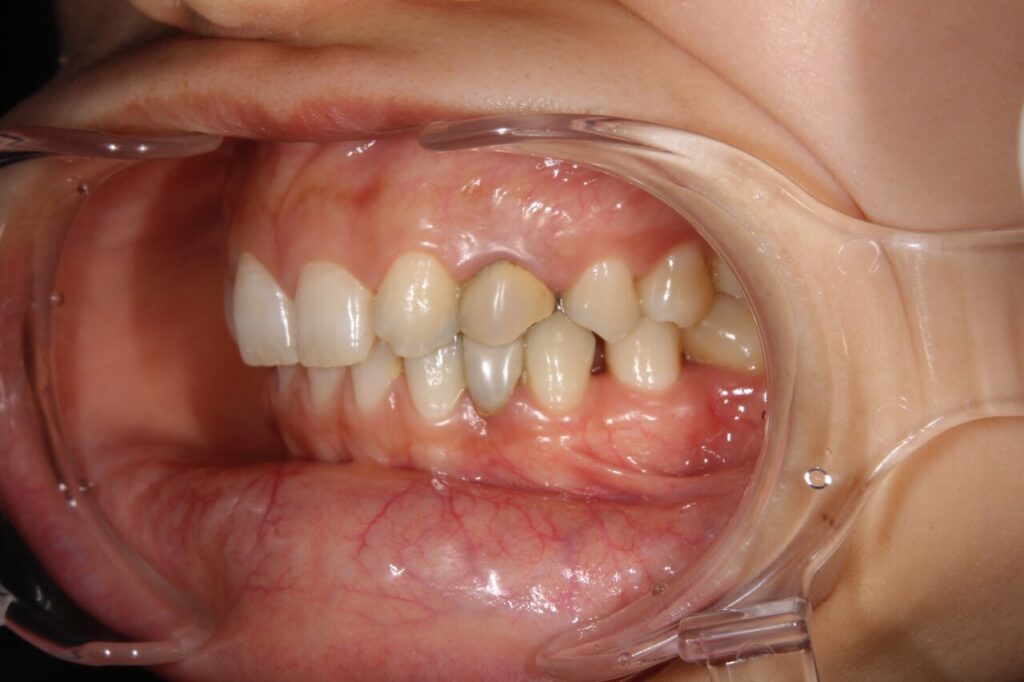

自由診療での接着ブリッジ(当院での自例)

保険診療では使える材料が金属のみですが

自由診療(自費診療)はその名前の通りに、制約がなく自由に材料や治療方法を選択できます。

主にセラミックやジルコニアを使った治療が多く

外れる可能性、割れる可能制はありますが、金属を使わないので見た目がきれいになります。

実際の当院での事例ですが

この方も乳歯が残っていたのが抜けてしまい、当時県外で保険診療で接着ブリッジを入れたそうです。

上下の歯をやりかえていきましたが、上の歯は虫歯や奥の削られていた歯の形の問題で通常のブリッジをセラミックで修復、下の歯は接着ブリッジでやりかえました。